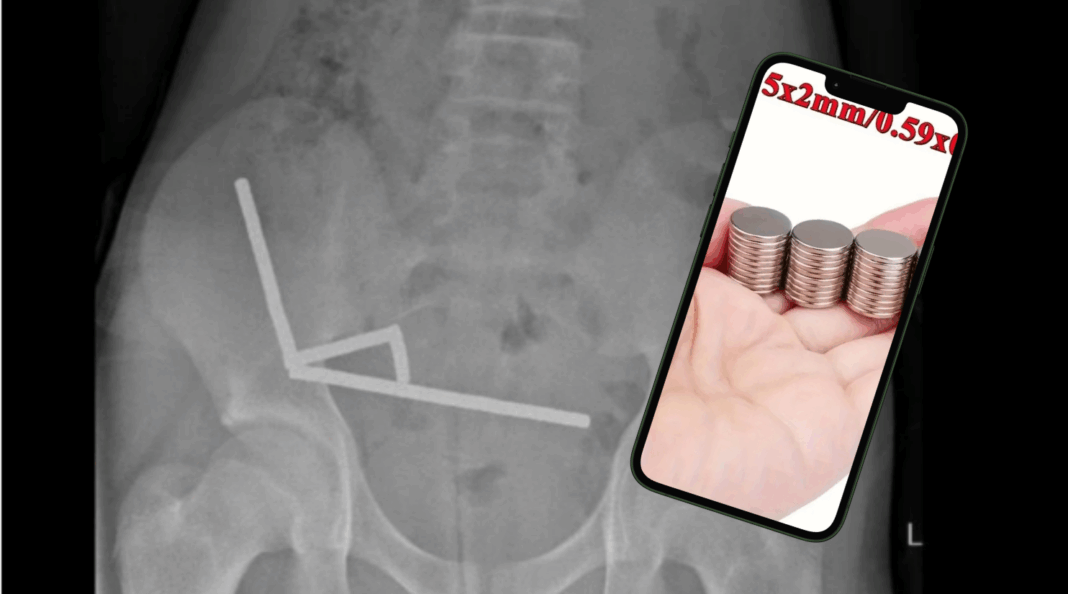

Según el reporte publicado en el New Zealand Medical Journal, el niño acudió a un centro médico debido a malestares estomacales, y las radiografías revelaron la presencia de «cuatro cadenas lineales de imanes» adheridos en diferentes partes de su intestino. Estos imanes, de aproximadamente 5 x 2 milímetros cada uno y de alta potencia (neodimio), habrían sido adquiridos por el menor a través de Temu.

Debido a la gravedad de la situación, el niño tuvo que ser sometido a una cirugía de emergencia en la que le extirparon parte de sus intestinos. Según el estudio, la ingestión de cuerpos extraños, si bien es común en pacientes pediátricos, «puede tener consecuencias graves como necrosis por presión, perforación y fistulación».